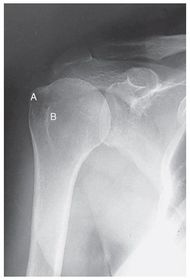

A. coracoid process B. glenoid cavity OR scapulohumeral joint C. spine of the scapula D. acromion